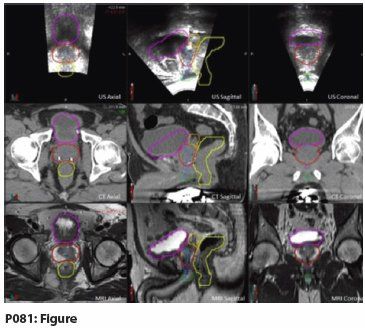

P081: Figure

Results: When comparing the contoured images on the MRI and TPUS, it is apparent that both modalities are superior to CT and similarly capable of demarcating soft tissue anatomy, such as the penile bulb (green), bladder (magenta), urethra (blue), genitourinary diaphragm (purple), prostate (red), seminal vesicles (orange), and rectum (yellow). We have provided an example of an MRI-contoured structure set overlaid on CT and US to visually portray this observation. The advantage of the TPUS during simulation and treatment can be extrapolated from these contoured images. These images may also serve as an atlas to delineate structures that can be visualized during radiotherapy.